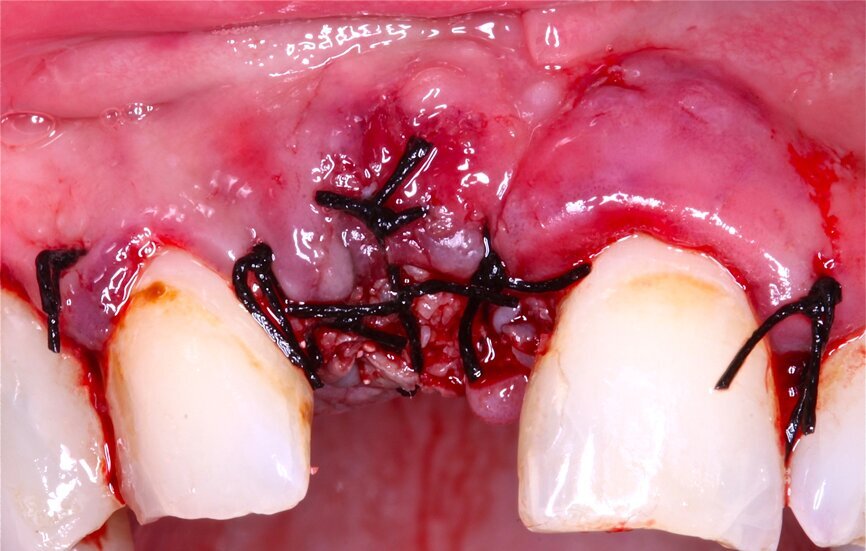

2. Sutura del colgajo con puntos simples y colchoneros horizontales con sutura 4/011,12.

TECNICA EN DOS FASES O SANDWICH13

Fig. 7 Figura 7

1. Anestesia infiltrativa vestibular y lingual o palatina de la zona a intervenir.

2. Incisión paracrestal 2 mm hacia palatino con hoja de bisturí 15C e intrasurcular a los dientes adyacentes.

Fig. 8 Figura 8

1. Elevación del colgajo mucoperióstico a espesor total con periostotomo exponiendo el defecto en su totalidad.

2. Desbridamiento de todo el tejido blando y granulomatoso presente en el defecto con la ayuda de cucharillas quirúrgicas.

Fig. 9 Figura 9

1. Determinación de la posición del implante con la ayuda de férula quirúrgica y con una fresa redonda o lanceolada.

2. Continuar con el protocolo de fresado estándar.

Fig. 10 Figura 10

1. Inserción del implante, con una estabilidad primaria correcta y posición prostodóntica ideal.

2. Realización de perforaciones en el lecho con fresa redonda para aumentar la disponibilidad de células osteogénicas y acelerar la revascularización y mejorar la unión injerto huésped.

Fig. 11 Figura 11

1. Relleno del defecto con biomaterial: "Técnica de Sandwich".

• 1a Capa: hueso autólogo o hueso particulado de reabsorción rápida.

• 2da Capa: hueso particulado de reabsorción lenta.

1. Recubrimiento de la zona regenerada con membrana reabsorbible, adaptándola y extendiéndose 2 mm por fuera del defecto.

Fig. 12 Figura 12

1. Reposición del colgajo mucoperióstico, en el caso de la liberación del perióstico para garantizar un colgajo sin tensión, cierre primario del lecho10.